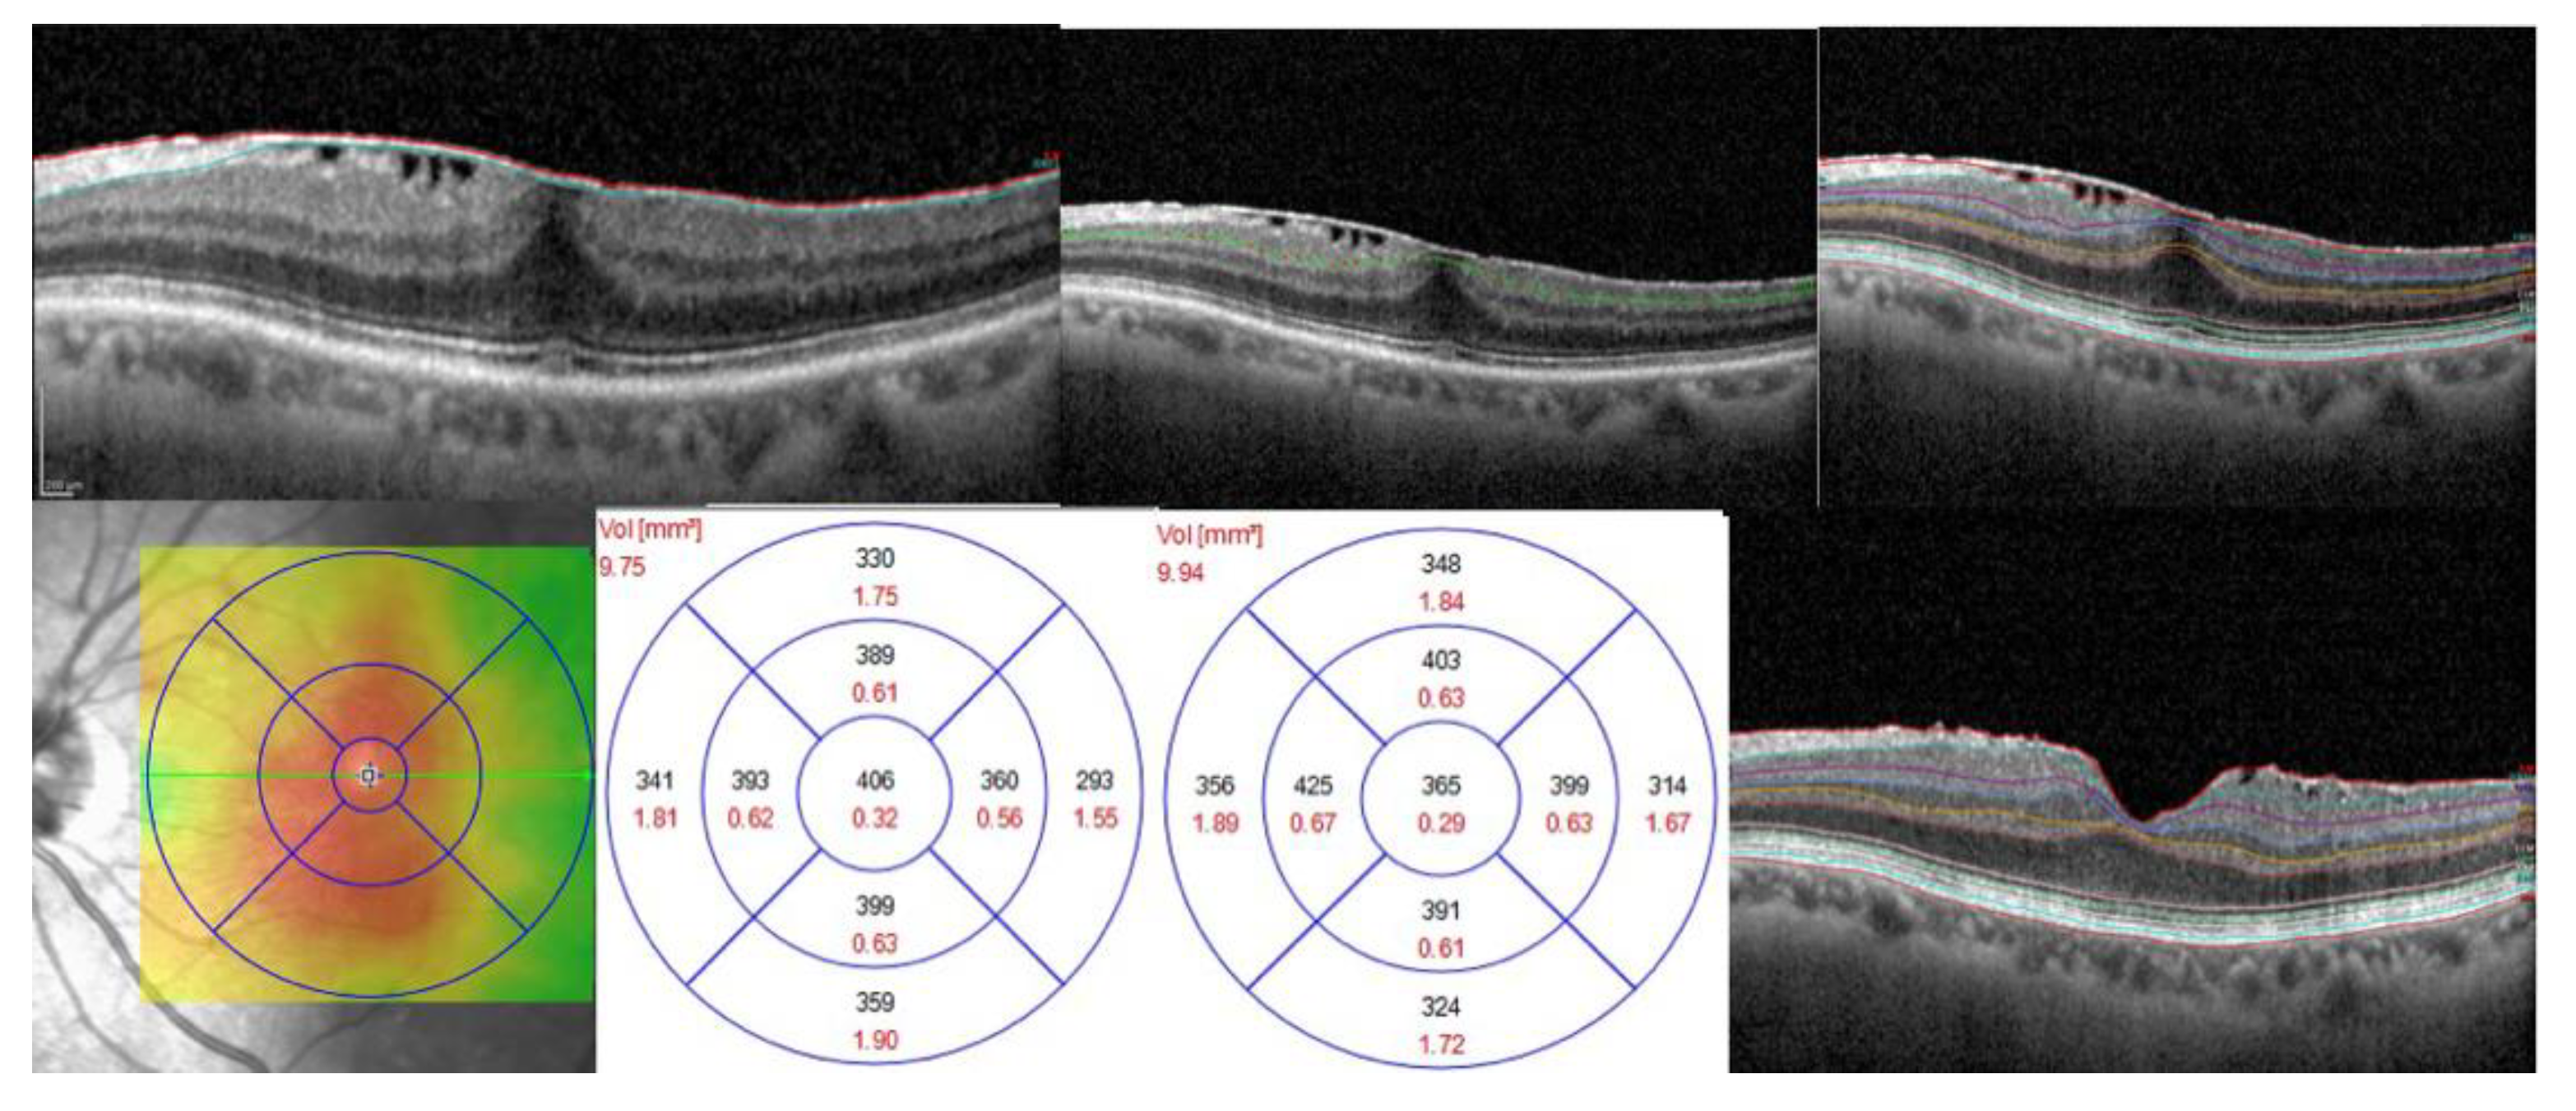

Distinctive OCT Thickness Variation Trends for Each Group